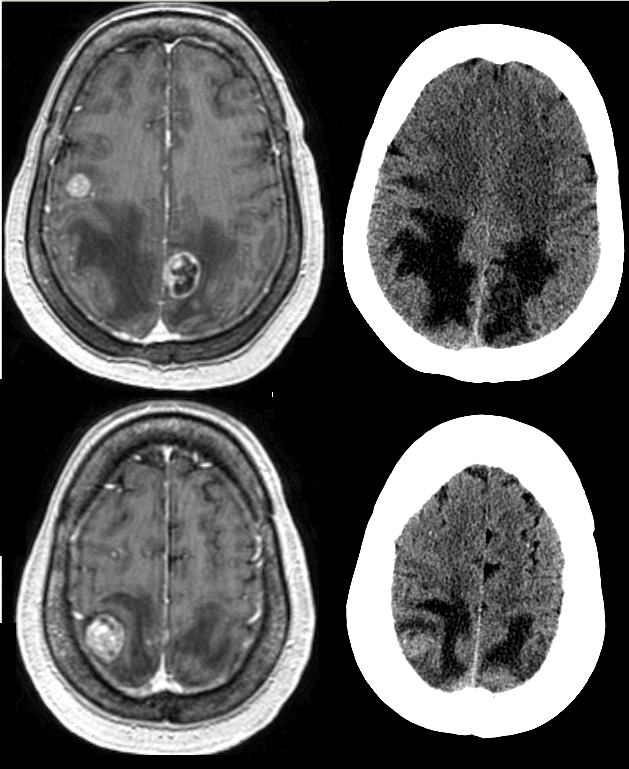

Initial interpretation based on posterior hypodensity was like PRES (Posterior Reversible Encephalopathy Syndrome) especially given recent paclitaxel and carboplatin use (both of which have been associated with PRES). Subsequent MRI with and without contrast, however, showed multiple enhancing lesions, suggesting metastatic disease without PRES.